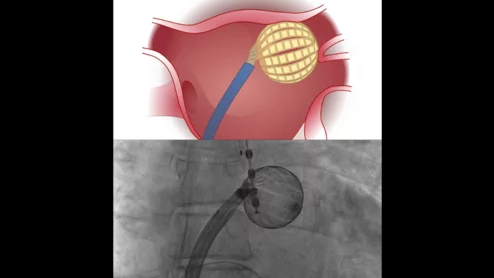

The next generation Watchman device is designed to better seal off complex LAA anatomy to prevent strokes in atrial fibrillation patients. It uses an optimized architecture to fill gaps and adapt to the unique characteristics of each patient's appendage, which come in a wide variety of shapes and sizes.

The next generation Watchman device is designed to better seal off complex LAA anatomy in a variety of LAA shapes and sizes.